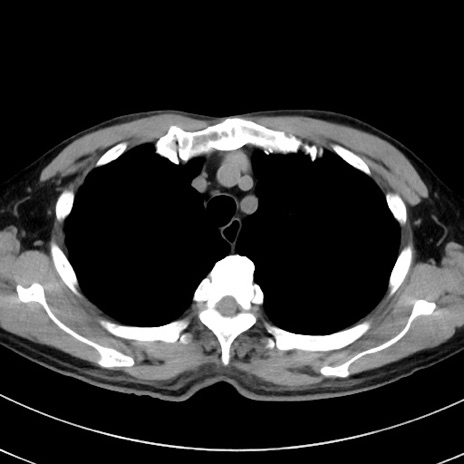

症例38(横断像)

【症例】70歳代 男性

【主訴】腹痛・嘔吐

【現病歴】昨晩より、嘔吐・腹痛あり。今朝になっても嘔吐あり。来院。

【既往歴】心臓バイパス手術、開腹胆摘、腸閉塞

【身体所見】BP 107/71mmHg、HR 116/min、腹部:平坦、軟、下腹部に軽度圧痛あり。反跳痛なし。

【データ】WBC 15100、CRP 0.32